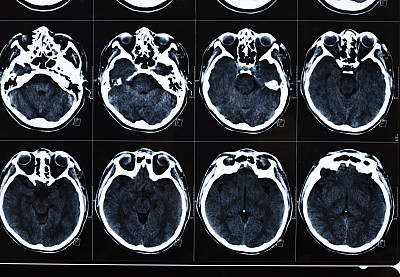

鞍结节脑膜瘤起源于脑膜细胞,通常生长缓慢。由于其位置特殊,可能会影响到视神经、垂体等重要结构,导致一系列神经系统症状。诊断主要依靠影像学检查,如MRI和CT扫描。